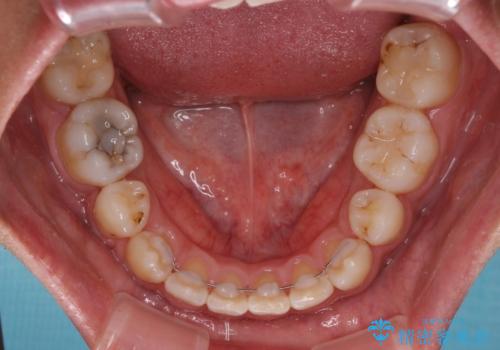

- 八重歯と上顎前歯の変色を気にして来院された患者様です。

上下ともに八重歯が顕著であったため、上下左右の第一小臼歯4本を抜歯し、ワイヤー装置での抜歯矯正を行うこととしました。

前歯は根管治療が必要な歯を事前に根管治療を行い、矯正治療後にオールセラミッククラウンにて補綴治療を行うこととしました。